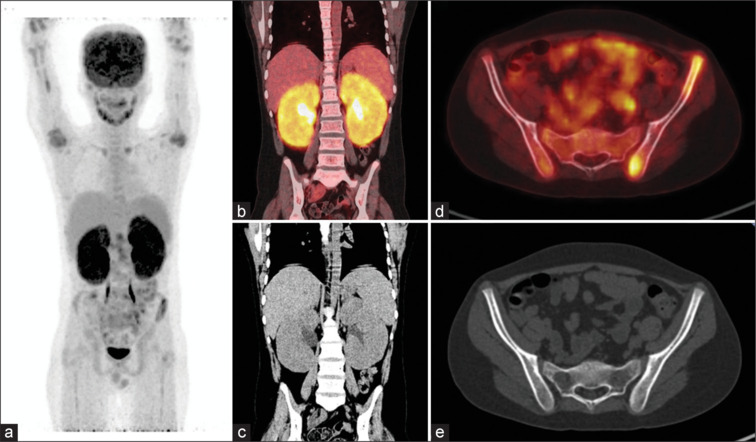

Acute lymphoblastic leukaemia (ALL) is a prevalent cause of paediatric leukaemia. Patients with ALL typically exhibit symptoms such as fever, bleeding, weight loss, and bone pain. Blood investigations results predominantly show anaemia and pancytopenia with blast cells in the peripheral smear. While ALL primarily affects the bone marrow, it can also impact nearly every organ. There have been previous reports of extramedullary involvement of multiple organs in cases of ALL. This case represents a rare occurrence of 18F-fluorodeoxyglucose (FDG) avid symmetrically enlarged kidneys as initial presentation of ALL.